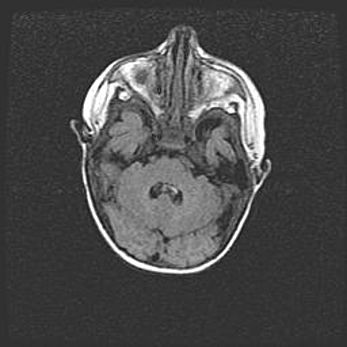

Множественные кисты обоих полушарий головного мозга, наибольшая из них в правой затылочной области. Ассиметричная атрофическая гидроцефалия.

Возраст: 7 месяцев

Вес: 5660 г

Пол: мужской

Окружность головы: 41,5 см

Срок гестации: 28-29 недель

Кисты головного мозга развиваются в результате многоочаговых некрозов вещества мозга и возникают вследствие перенесенной перинатальной инфекции, менингитов, энцефалитов, асфиксии, родовой травмы, расстройств мозгового кровообращения различного генеза. Образованию кист в веществе головного мозга плодов и новорожденных способствуют такие факторы, как высокое содержание в нем воды, недостаточная (или отсутствие) миелинизация и слабая астроглиальная реакция на повреждение.

Кисты могут сочетаться с гидроцефалией и другими поражениями головного мозга.